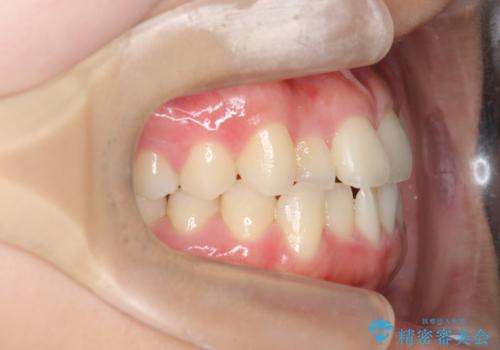

マウスピース矯正で前歯のガタつきを改善

- 上下の前歯のガタつきの改善を求めて、矯正治療を希望され来院されました。

矯正検査の結果、マウスピース矯正システム インビザラインの適応であることからワイヤーを用いず矯正治療を進めることとしました。

1日20時間以上の使用時間をきっちりと守っていただけたため、良好な治療結果、歯並びを手に入れることができました。